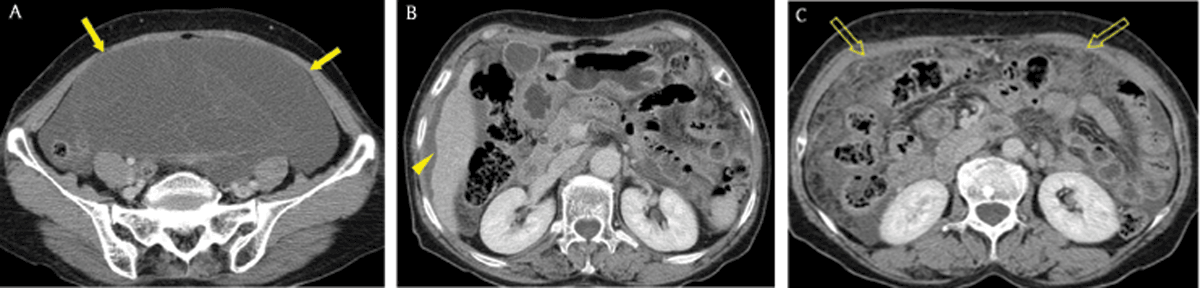

Figure 9

A 74-year-old woman with tuberculous peritonitis. Axial portal venous phase CT images showed multiple nodules (arrowheads), diffuse peritoneal thickening (arrow), ascites, and omental haziness (open arrow), findings that mimicked peritoneal carcinomatosis.